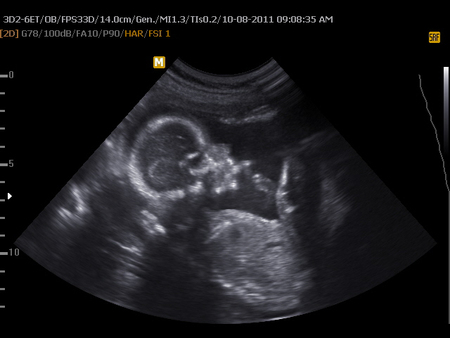

Нам 27 неделек и 3 дня)

Ну вот, как писала в предыдущем сообщении - была сегодня в ЖК. Вчерашние анализы хорошие. Сделали УЗИ: предлежание - главное, положение плода - продольное, движения плода - активные, сердцебиение - ритмичное, ЧСС - 140 уд. / мин, рост плода - 34см, вес плода - 1028г, БПР - 70мм, ОЖ-74мм, ДГрК-64мм , ДлБ - 51мм, количество околоплодных вод - нормальная (50мм), локализация плаценты - передняя, степень зрелости плаценты - 1, толщина плаценты - 27мм, пуповина: количество сосудов - 3, патологические отклонения, пороки развития плода - не обнаружено. Заключение УЗИ: По биометрии беременность 27-28 недель.

И конечно еще раз подтвердили, что будет пацанчик))) И все было прекрасно, пока врач не стал делать допплерометрии кровотока в артерии пуповины .. Минут 7 напряженно смотрел на экран, спросил как я себя чувствую ... Потом написал заключение и сказал немедленно идти к своей Г.. И тут мое сердце бешено забилось ... На пути к ее кабинету раз 5 перечитывала то заключения и ничего не поняла, а писало там вот что: СДО - 4,5 (норма - 3,7), ИР - 0,7 (в норме ), ПИ - 1,3 (норма - 1,09). Вывод: замедленный кровоток.